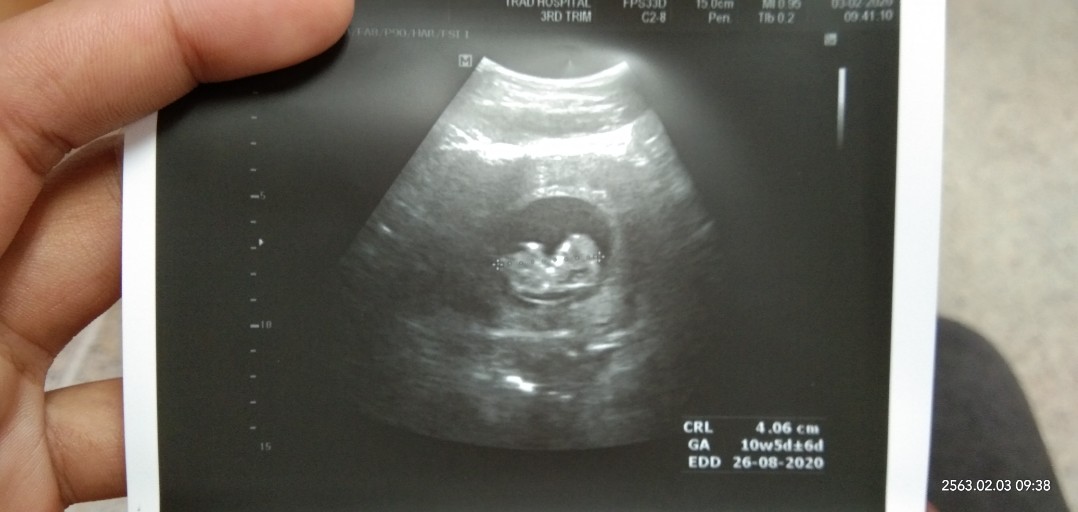

10w ค่ะ